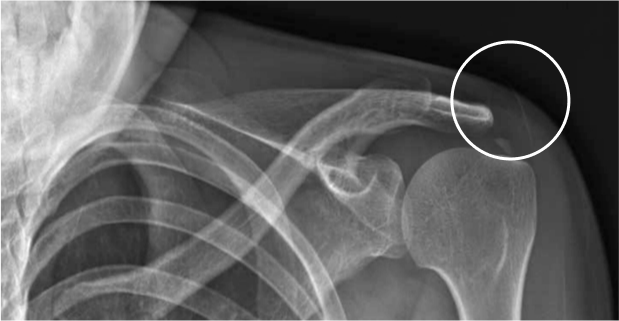

석회화건염

석회성물질이 어깨에 쌓여 힘줄에 통증을 유발시키는 질환입니다. 주로 30~50대에서 발생하고 있습니다.

과도한 어깨 사용으로 힘줄이 손상되어

석회가 쌓이는 것이 주요 원인!

대표적인 증상

• 외상은 없으나 통증이 지속

• 전면 삼각근 부위에 통증 발생

• 뽀족한 물건으로 쑤시는 듯한 날카로운 통증

• 팔, 어깨를 들어올리기 어려움

• 야간에 잠을 이루기 어려울 정도의 심한 통증